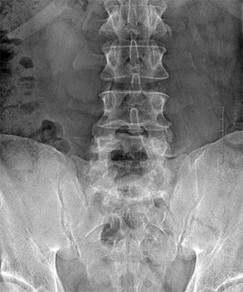

A 65-year-old female presents with progressive stooped posture, early satiety, and severe low back pain. Radiographs reveal degenerative adult spinal deformity.

Which of the following spinopelvic parameters is most strongly correlated with poorer health-related quality of life (HRQOL) outcomes if it exceeds normative thresholds?